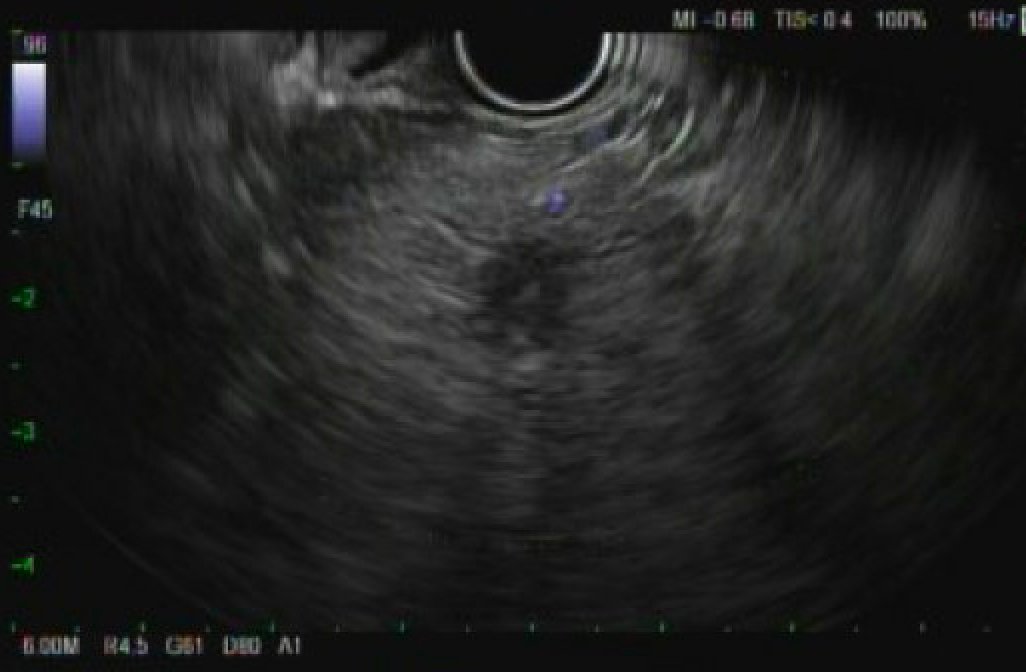

@AnandSahaiEUS @EHolzwanger @NEndoscopy @JChristieMD @amolbapaye @DrSalihTokmak @tberzin @Taalamri @KM_Pawlak @drKumarGI @KMonkemuller @BilalMohammadMD @drkeithsiau @TrieuMD @sahajrathi @DannyIssaMD From the picture area is not having a clear border and no clearly homogeneous. I would think fat sparing. Normal PD also goes against it. Biopsy increases the risk of pancreatitis. Short interval follow up and Ca19-9 will be a good choice too.

@EHolzwanger @NEndoscopy @JChristieMD @amolbapaye @DrSalihTokmak @tberzin @Taalamri @KM_Pawlak @drKumarGI @KMonkemuller @BilalMohammadMD @drkeithsiau @TrieuMD @sahajrathi @DannyIssaMD Wondering why anyone would not biopsy...

You're doing a thorough scan of a fatty pancreas and you come across this slight hypoechoic area in the BOP as seen in the photos attached? Do you sample? If so, why and what do you think it could be? #GITwitter #MedEd @NEndoscopy @JChristieMD @amolbapaye @DrSalihTokmak @tberzin